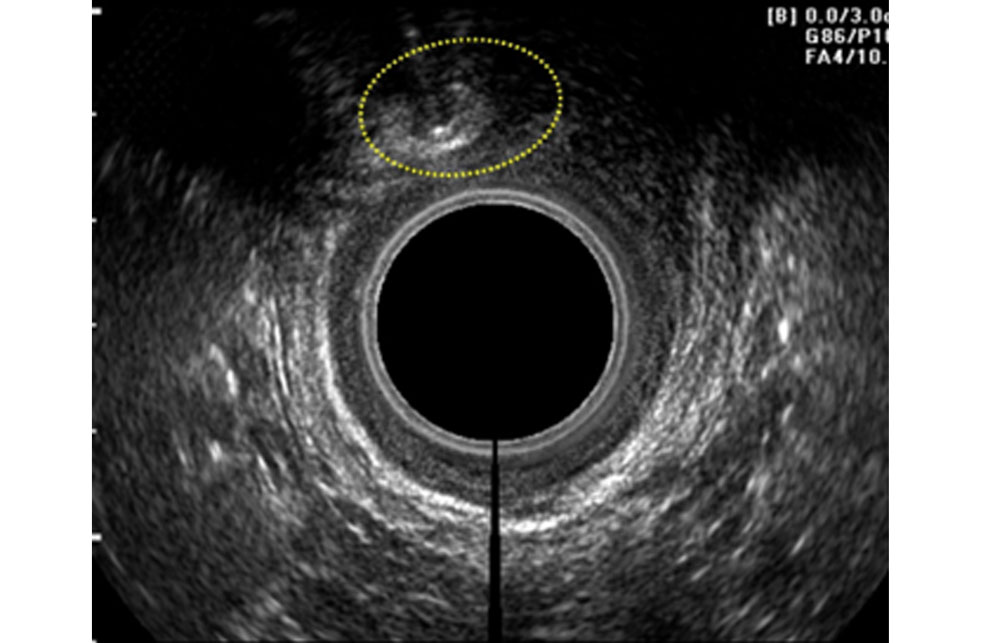

Fig 2 - Inoculazione del prodotto LIPOGEMS sotto guida Ecografica endoanale

Qualora fosse necessario praticare un vero e proprio intervento chirurgico, l’ associazione della tecnica rigenerativa con inoculazione del prodotto LIPOGEMS®, che a seconda delle differenti situazioni può venire effettuata nella area chirurgica, intorno al bordo anale, nello spazio intersfinterico e lungo il decorso dei nervi pudendi, sarà in grado di attenuare gli aspetti negativi postoperatori ottenendo una significativa riduzione del dolore e una più veloce guarigione delle ferite.